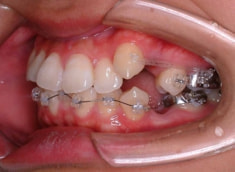

治療開始時

治療中のパノラマレントゲン

歯根吸収もなく、パラレリング(平行性)も確保されております。